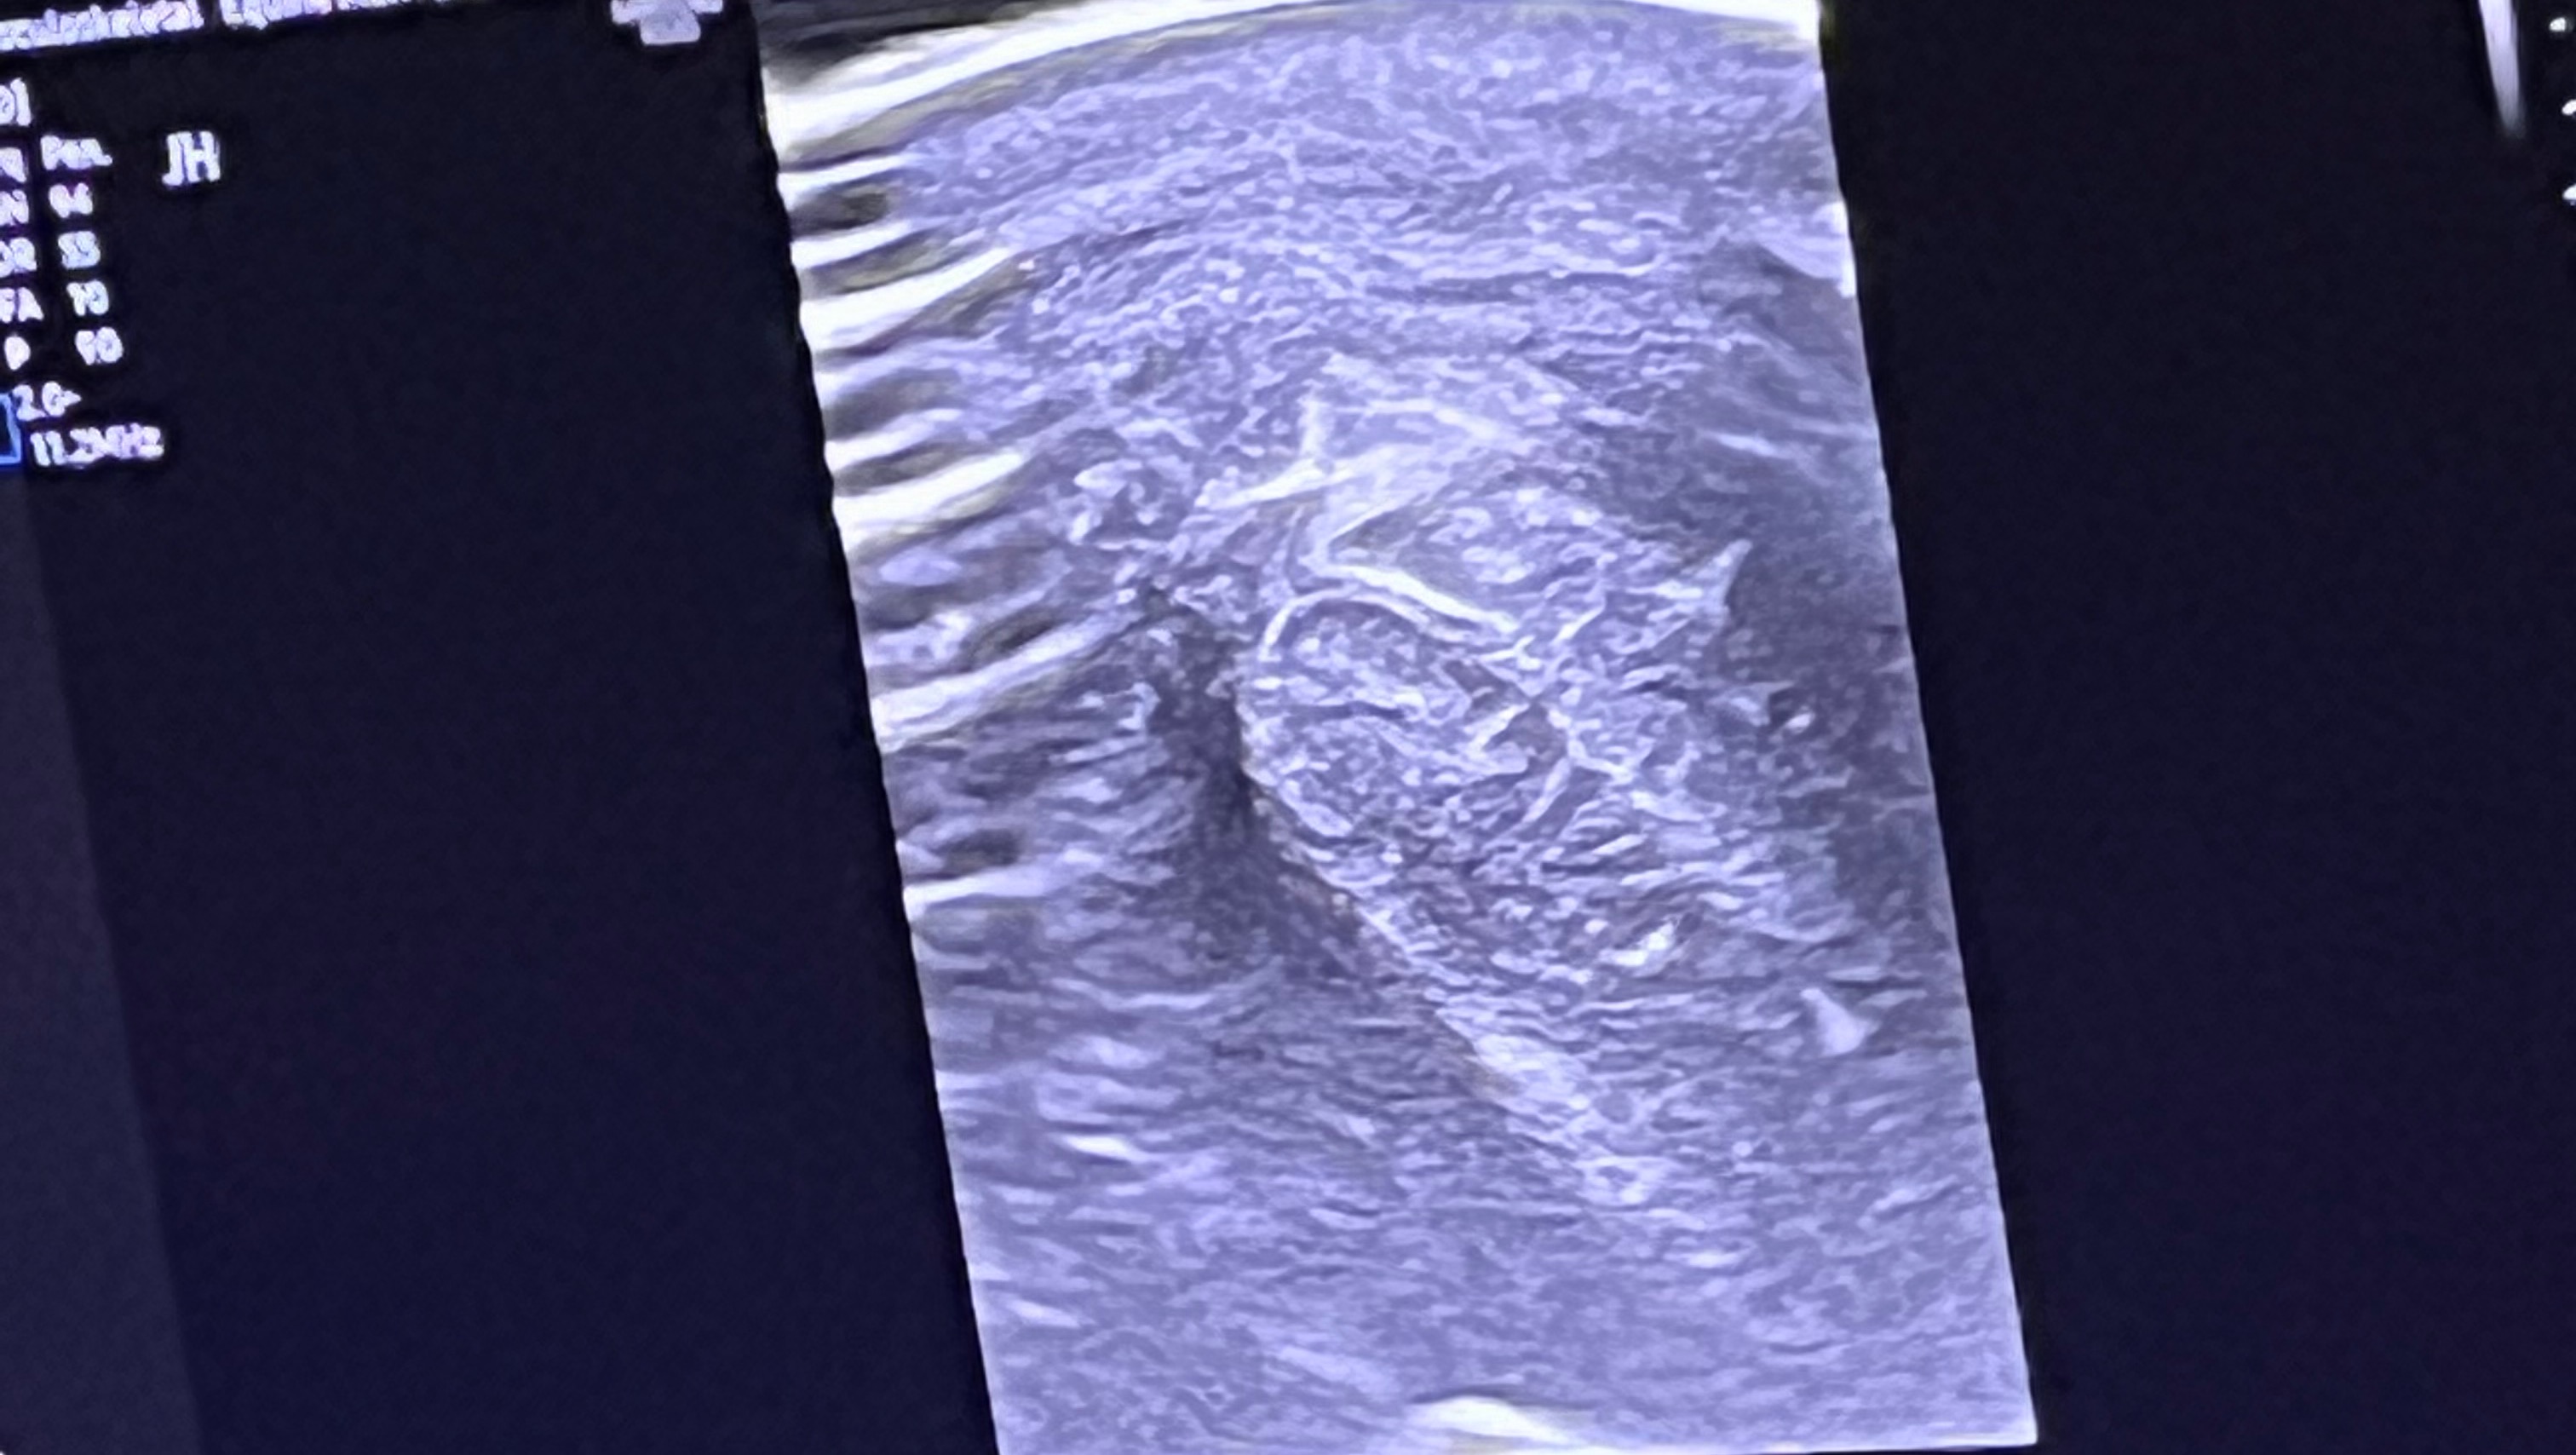

Unfortunately while taking a rider out for an adventure it seems he tore his Manica Flexora. This is a thin sheath that bundles all of the tendons together in the lower leg above the pastern. Because it is torn the tendons will keep rubbing on it getting lesions and making him limp.

But there’s hope! While it cannot be solved medically (with medicines and injections and the like), it can be solved with surgery that would go in and remove the torn portion of the membrane. And this surgery has a very high success rate (70% chance of getting back to full work). We actually had another one of our horses, Poco, have this surgery in the past, and she’s 100% better and even does endurance races again.

While no surgery is a guarantee, without the surgery, he will always have pain in that leg and inflammation of his tendons.